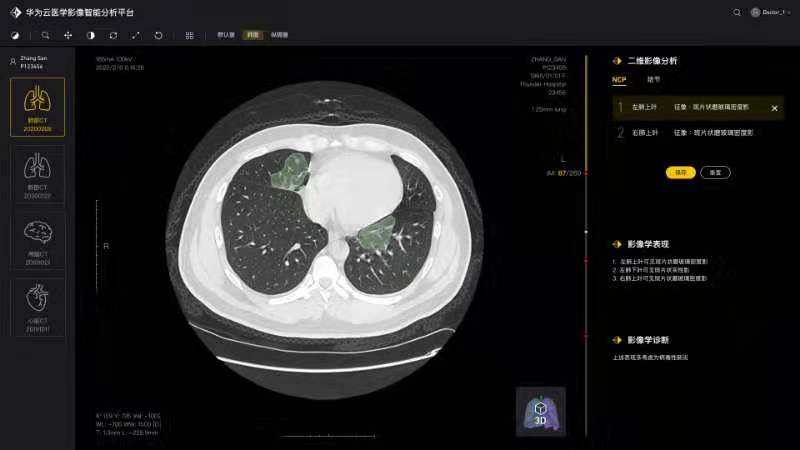

将论文写在祖国的大地上,加快加强疫情防控科研攻关,服务一线疫情防控救治——疫情发生以来,由学院白翔、许永超等老师负责的咕咕番

—华为智能创新实验室积极发挥自身优势,组织团队师生争分夺秒抓紧开展高质量科研攻关,与附属协和医院放射科、华为云、篮网科技等团队共同研发出一套基于人工智能技术的面向新冠肺炎肺部CT影像量化分析系统。2月29日下午,中共中央政治局委员、国务院副总理孙春兰率中央指导组来校考察疫情防控科研攻关情况,许永超副教授当场向孙副总理介绍了研发推出该系统的工作及成果。该系统可以辅助医生更高效地区分新冠肺炎的早期、进展期与重症期,有利于早期筛查与防控。同时,对于确诊病人,基于对多次复查影像数据的量化分析,医生能够有效评估病情进展及用药疗效等情况。目前该系统已在全国几十家医院使用,日均调用量3000多次。孙春兰肯定了研究团队所开发系统的精确性,可以辅助医生定量分析,大幅提升效率,缓解影像医生的压力。她非常关注该系统的落地应用情况,特别是在湖北省、武汉市的应用,鼓励团队结合CT影像与核酸试剂等信息,进行更为精准的新冠肺炎诊断。